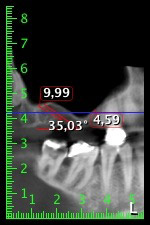

About six months after teeth 16 and 14 were extracted, a digital volume tomography (DVT, Planmeca) examination was performed for planning and risk minimization purposes. It clearly showed that the bone had not regenerated to the desired volume (Fig. 2 to 7).

Image 2 to 7: DVT with greatly reduced horizontal bone volume.

A sinus floor elevation was required in both regions 16 and 14 to guarantee a fixed restoration based on at least two implants. Relatively large-scale bone augmentation was required due to the residual bone volume being extremely low in this case. Major bone augmentation procedures are invasive and linked to higher patient morbidity, as well as being time-consuming and expensive. It is more difficult to predict the results of the treatment and the risk of failure is increased. The patient was informed of the increased risk and was offered a removable solution, which she consistently rejected.

To restrict the augmentation to region 14, and in consultation with the patient, it was planned that implant 16 would be placed, inclined, in the dorso-cranial direction (Fig. 8).